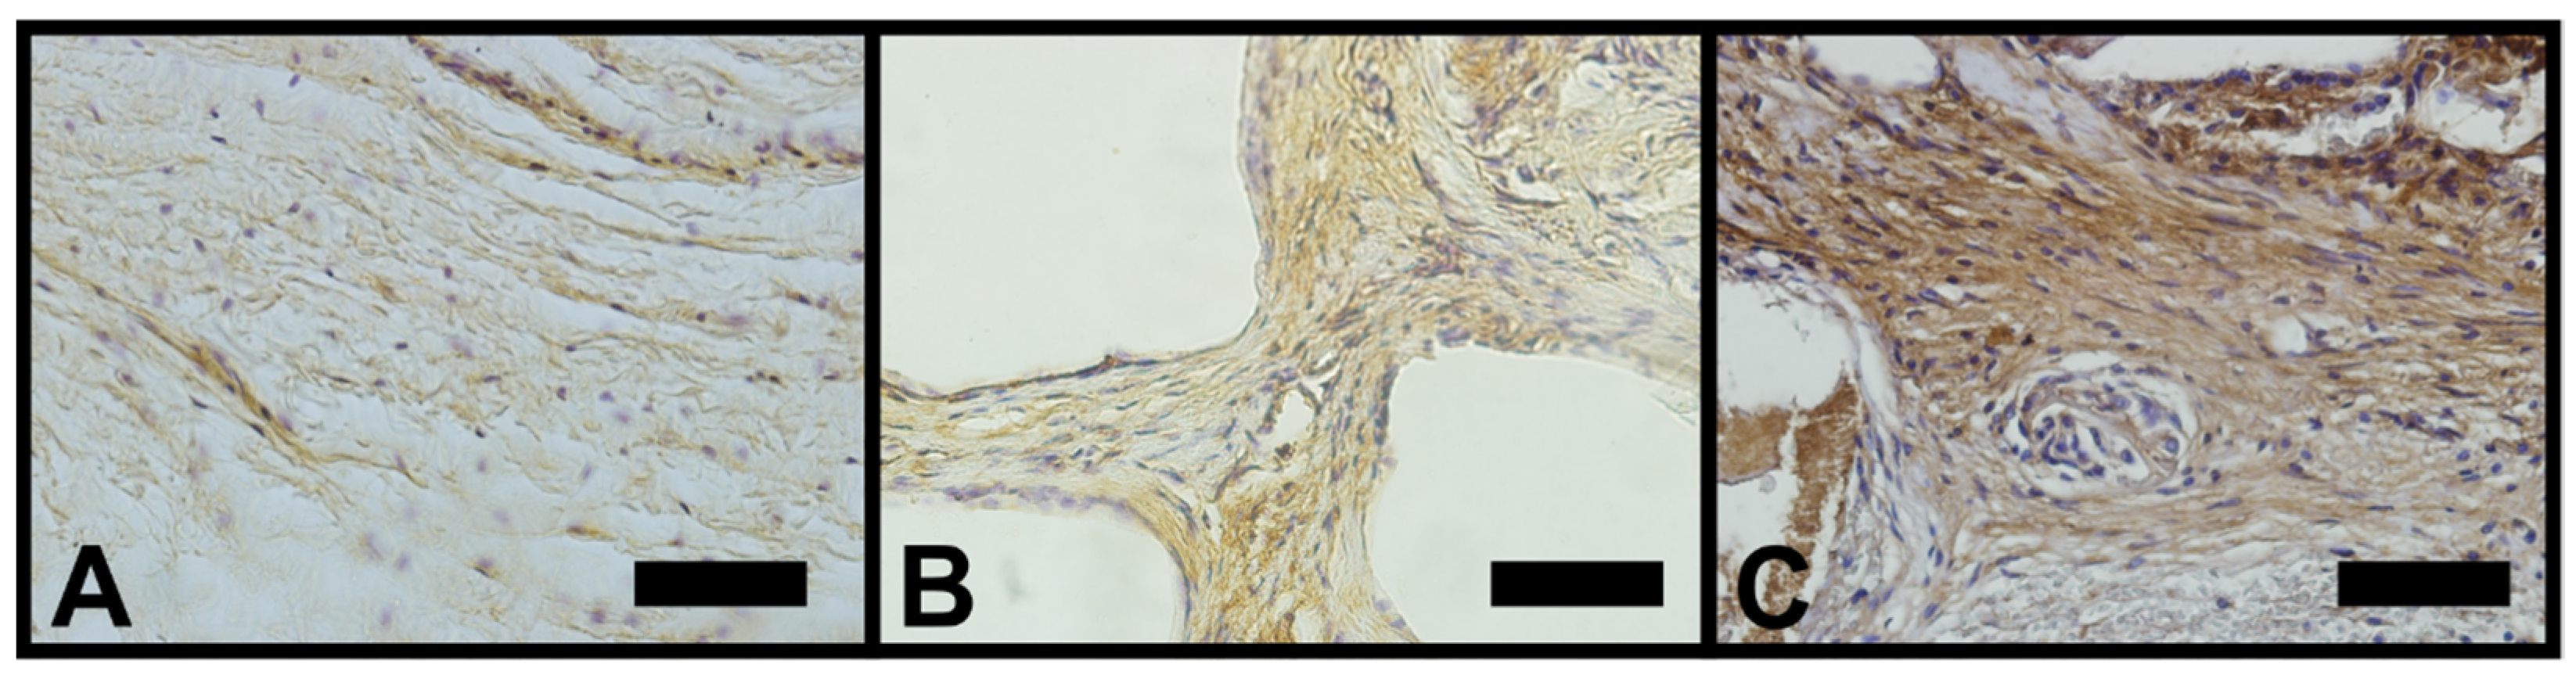

3.2. Osteopontin

3.3. Vascular Endothelial Growth Factor (VEGF)